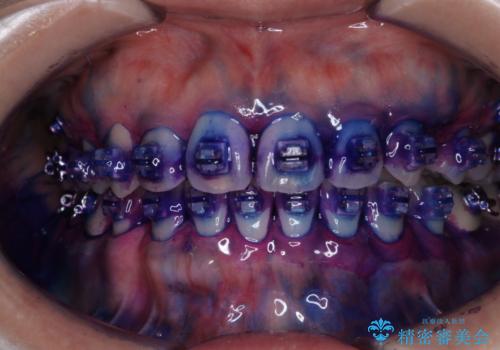

ワイヤー矯正中に歯の染め出し

- ワイヤー矯正中にクリーニンング希望とのことでした。染め出しを行い歯磨き指導とPMTC60分コースを行いました。

ワイヤー矯正中はブラッシングが難しくなるため、磨き残しが多くなることがあります。適切な道具を使って、適切なブラッシング方法を習得することで、磨き残しを減らすことができます。